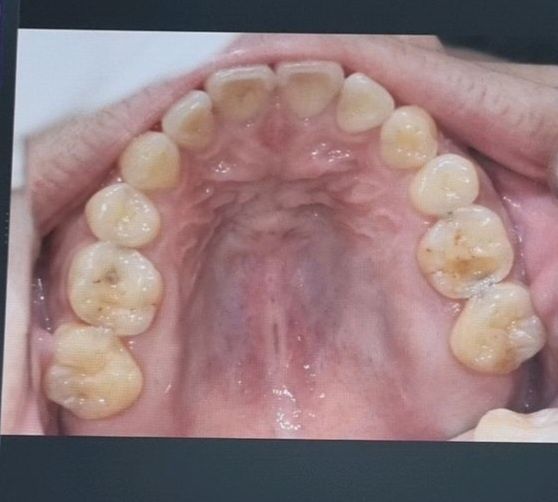

이갈이 치아 마모 및 충치 크라운치료 필요 여부

얼마 전 A치과 방문하여 위아래 어금니 7개 크라운 소견 받았습니다.

충치 및 이갈이로 인한 치아 파절 마모입니다.

치아 사진 첨부하였습니다.